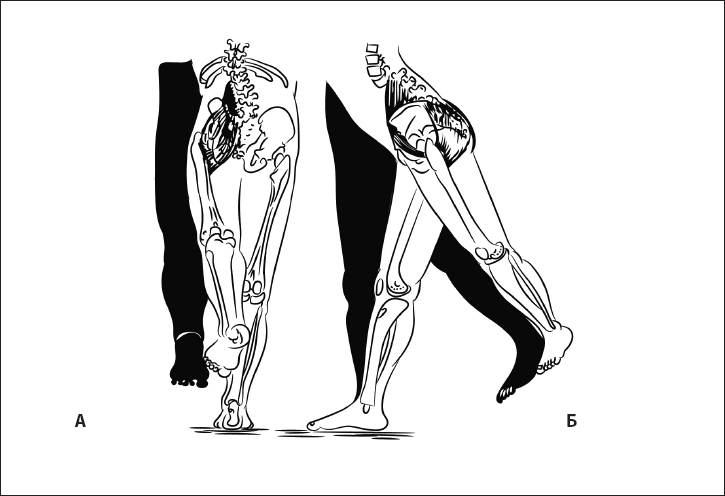

Рис. 25. Шаговый рефлекс, или автоматическая походка. А – норма, Б – отсутствие рефлекса.

Рис. 26. При правильном формировании паттерна шага туловище разворачивается навстречу ноге, согнутой в тазобедренном суставе (работа косых мышц живота). А – вид сбоку, Б – вид сзади.